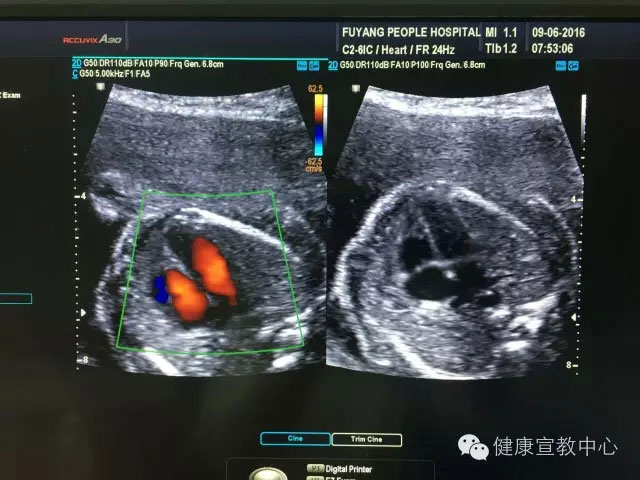

胎兒專項(xiàng)系統(tǒng)檢查是建立在胎兒中孕系統(tǒng)超聲檢查的基礎(chǔ)上對(duì)所篩查的器官、作更系統(tǒng)化精細(xì)化檢查。從2015年,開展胎兒專項(xiàng)系統(tǒng)篩查(胎兒心臟、胎兒中樞神經(jīng)系統(tǒng)、顱腦微小畸形、脊柱等)以來(lái),共計(jì)完成400余例。目前,該項(xiàng)技術(shù)處于省內(nèi)領(lǐng)先水平,部分省級(jí)醫(yī)院還尚未開展。

(胎兒超聲心動(dòng)圖)